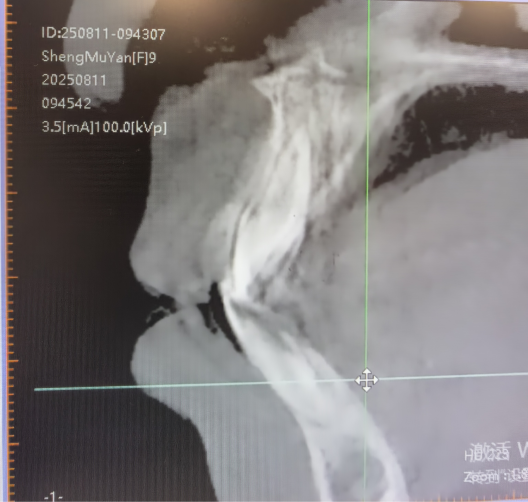

(要闻8)9 岁女童“地包天” 早期矫治见成效

近期,一名9岁女童“地包天”早期矫治显成效——通过混合牙列阶段的精准干预,不仅解决了咬合问题,更实现了面型的美观蜕变。

我院口腔中心医生提醒家长:若发现孩子咬合或面型异常,应尽早就诊,抓住生长发育关键期实现“颜值与功能”的双重改善。